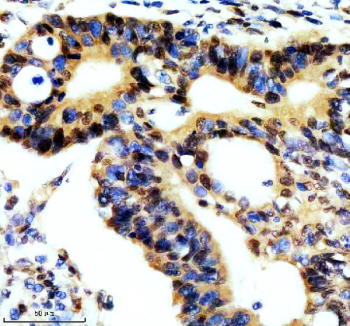

Immunohistochemical staining of REST using anti-REST antibody. REST was detected in a paraffin-embedded section of human colon cancer tissue. Heat mediated antigen retrieval was performed in EDTA buffer (pH 8.0, epitope retrieval solution). The tissue section was blocked with 10% goat serum. The tissue section was then incubated with 2 ug/ml rabbit anti-REST antibody overnight at 4oC. Peroxidase Conjugated Goat Anti-rabbit IgG was used as secondary antibody and incubated for 30 minutes at 37oC. The tissue section was developed using an HRP secondary and DAB substrate.